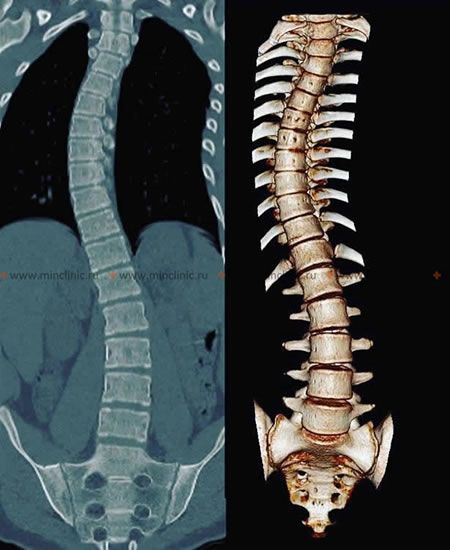

ხერხემლის სკოლიოზის დიაგნოსტიკისათვის გამოიყენება ორთოპედიული გასინჯვა, ასევე ხერხემლის რენტგენოგრაფია პირდაპირ და გვერდით პროექციაში, ხერხემლის კომპიუტერული ტომოგრაფია (CT). ბავშვობის ასაკში გამოვლენილი სკოლიოზისა და წელში მოხრილობის მკურნალობა ბავშვისა და მშობლის მხრიდან დიდ მოთმინებას მოითხოვს.

იდიოპათიკური სკოლიოზი ხერხემლის კომპიუტერულ ტომოგრაფიაზე (CT).